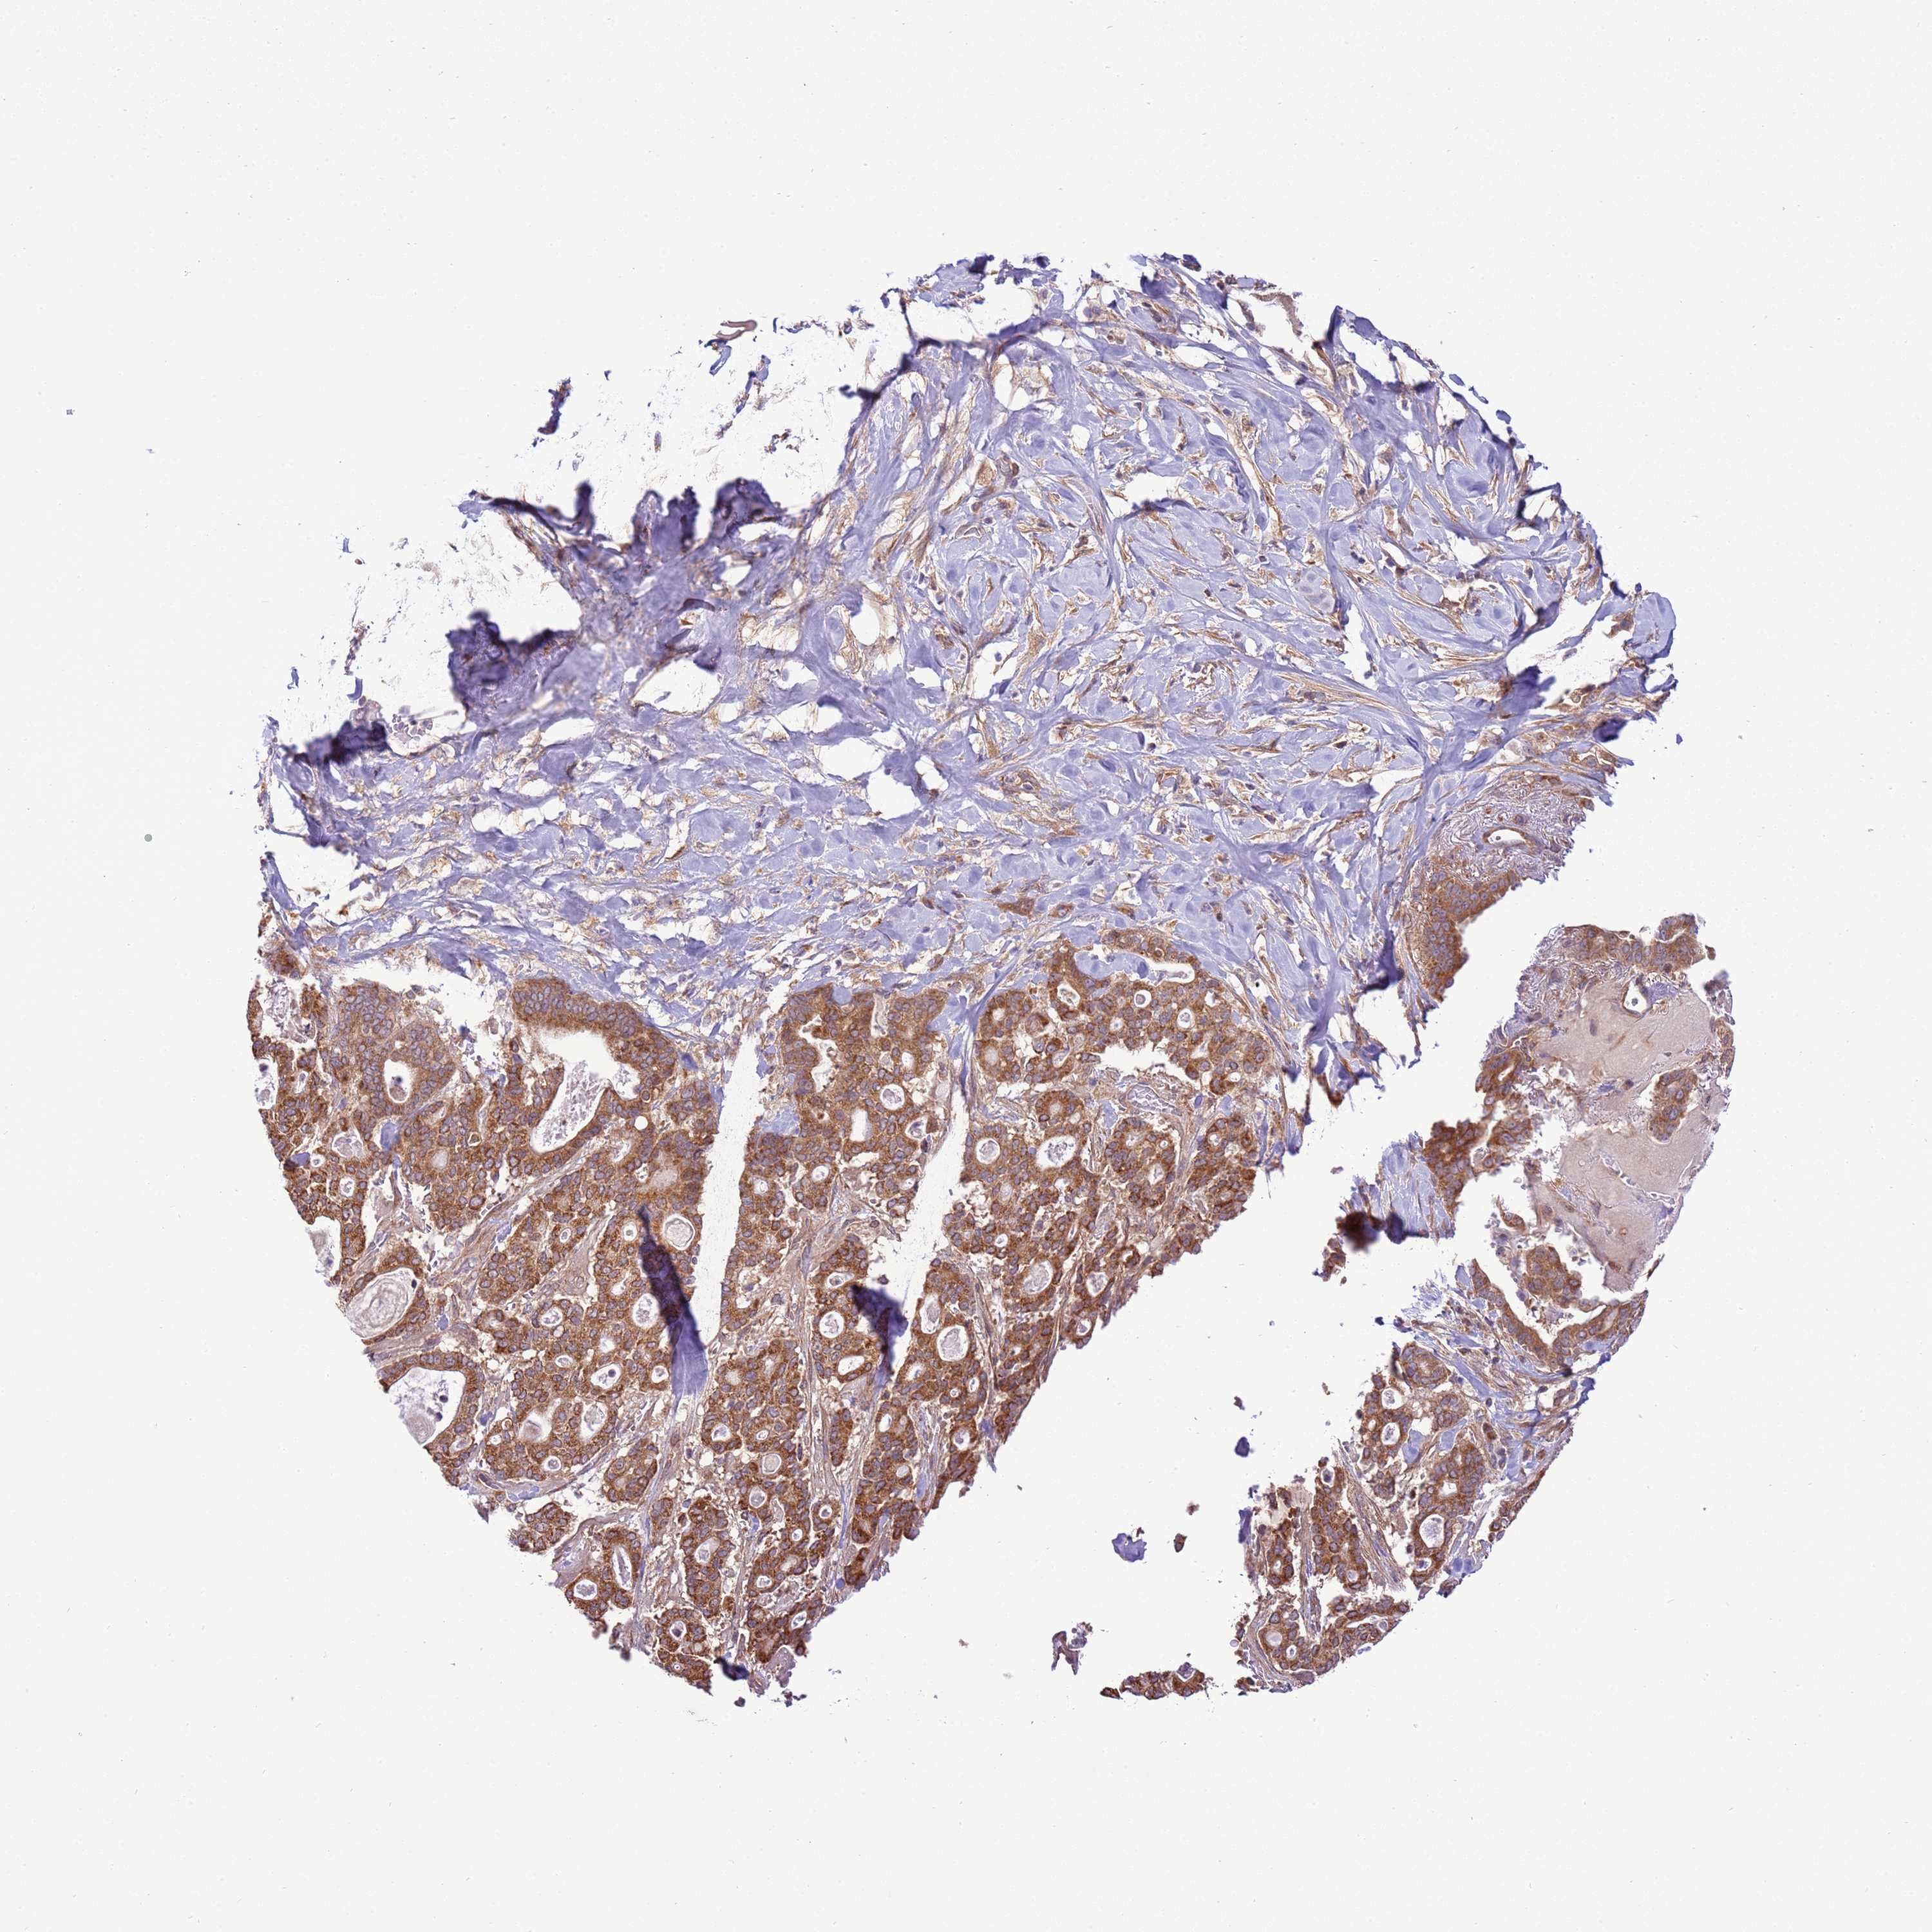

PANCREATIC CANCER - Protein expressioni

A mouse-over function shows sample information and annotation data. Click on an image to view it in a full screen mode. Samples can be filtered based on level of antibody staining by selecting one or several of the following categories: high, medium, low and not detected. The assay and annotation is described here.

Note that samples used for immunohistochemistry by the Human Protein Atlas do not correspond to samples in the TCGA dataset.

Antibody stainingi

Antibody staining in the annotated cell types in the current human tissue is reported as not detected, low, medium, or high, based on conventional immunohistochemistry profiling in selected tissues. This score is based on the combination of the staining intensity and fraction of stained cells.

Each image is clickable and will lead to virtual microscopy that enables deeper exploration of all samples and also displays staining intensity scores, fraction scores and subcellular localization as well as patient and tissue information for each sample.

Antibody HPA047386

Staining

High

Medium

Low

Not detected

Intensity

Strong

Moderate

Weak

Negative

Quantity

>75%

75%-25%

<25%

None

Location

Nuclear

Cytoplasmic/membranous

Cytoplasmic/membranous,nuclear

Adenocarcinoma, NOS